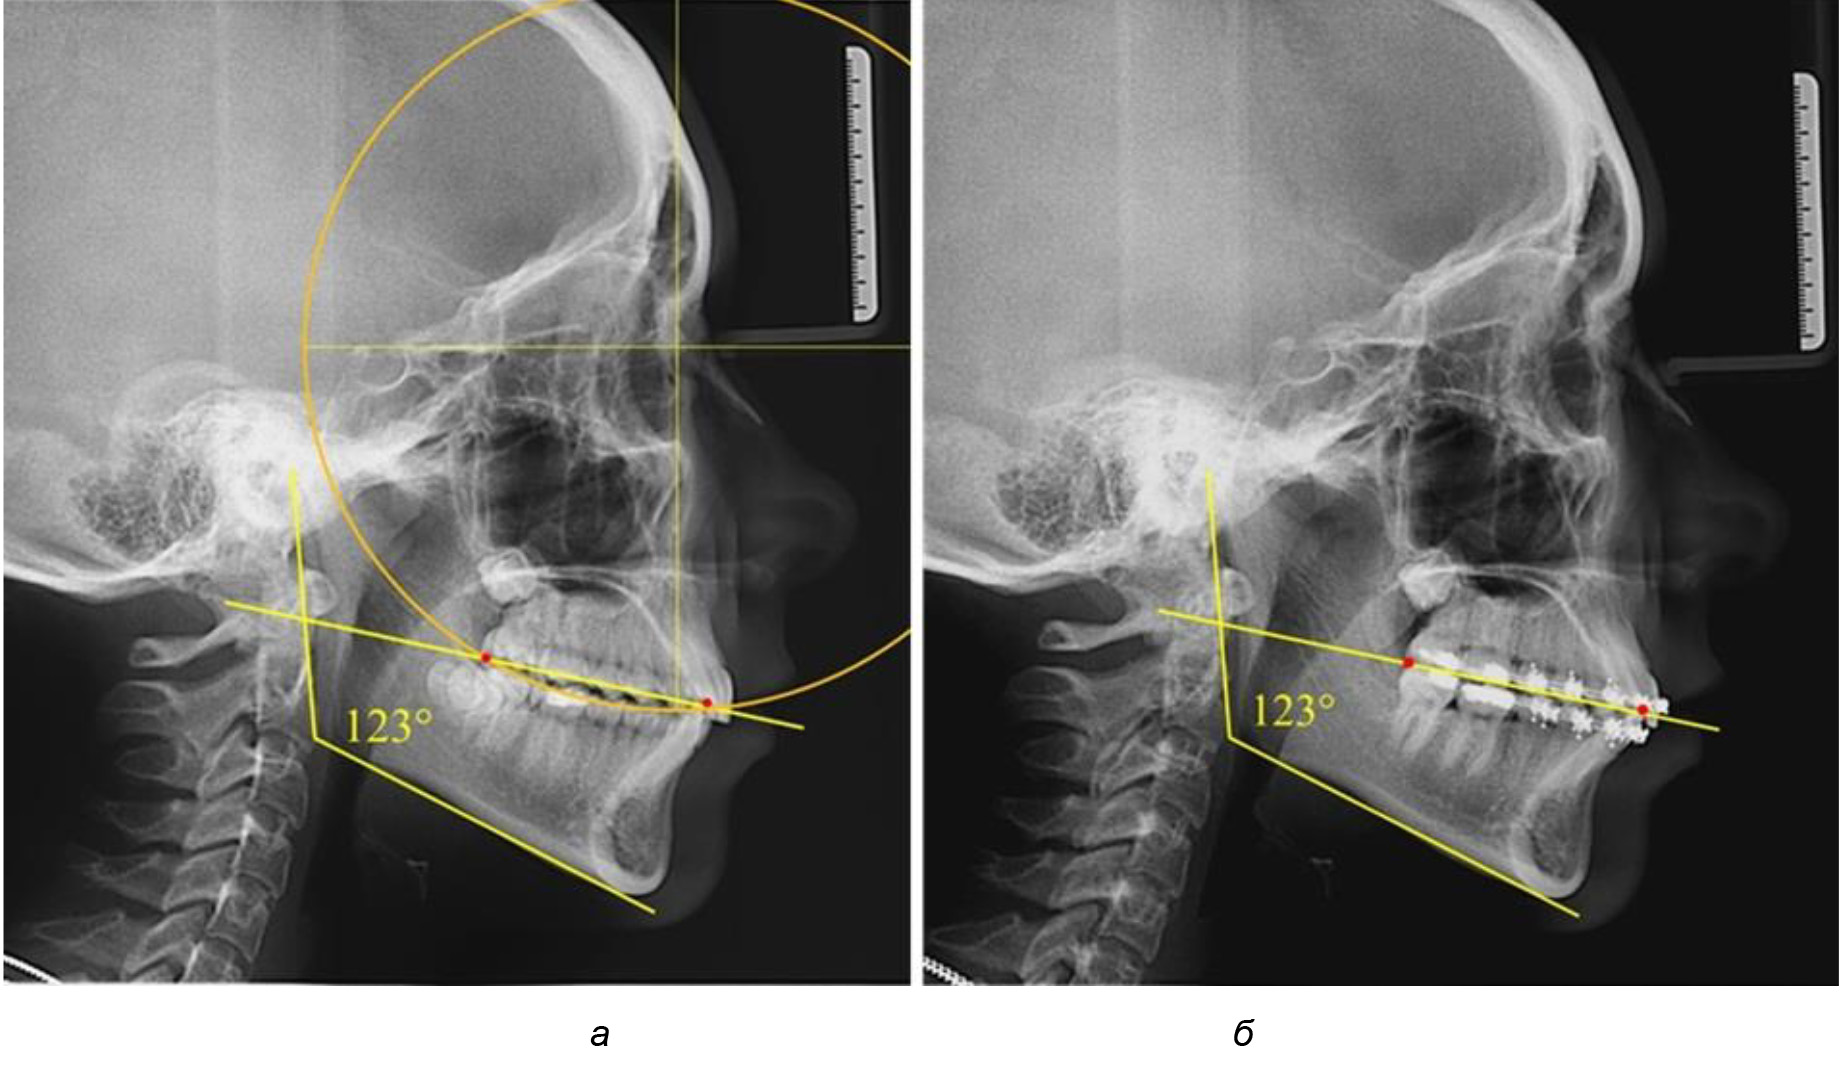

Рис. 5. Особенности ТРГ при патологической кривой Spee до лечения (а) и после лечения (б) техникой «прямой» дуги

После лечения пациентов техникой «прямой» дуги, так же как и в 1-й подгруппе, было отмечено увеличение сагиттального размера окклюзионной лини в среднем на (2,38 ± 0,83) мм. Окклюзионная линия практически касалась окклюзионного контура всех жевательных зубов, и отмечалось практически полное отсутствие кривой Spee, так же как и у людей 1-й подгруппы 2-й группы (рис. 6).

Рис. 6. Особенности ТРГ при оптимальной кривой Spee до лечения (а) и после лечения (б) техникой «прямой» дуги

Глубина кривой Spee в среднем по 2-й подгруппе составила (5,69 ± 1,57) мм, что было достоверно больше, чем у людей с физиологической окклюзией (р ˂ 0,05). Достоверных различий с показателями, полученными при анализе ТРГ и ОПТГ, нами не отмечено (р ˃ 0,05). Отношение радиуса окружности к сагиттальному размеру окклюзионной линии в среднем по подгруппе составляло 1,372 ± 0,042 и не соответствовало числу Фибоначчи, что может быть использовано в качестве диагностического критерия определения патологической формы кривой Spee. После лечения пациентов техникой «прямой» дуги было отмечено незначительное увеличение сагиттального размера окклюзионной лини в среднем на (2,12 ± 0,77) мм. Однако окклюзионная линия практически касалась окклюзионного контура всех жевательных зубов, и отмечалось практически полное отсутствие кривой Spee.

Таким образом, проведенное лечение техникой «прямой» дуги способствует нормализации окклюзионного равновесия и торку передних зубов, однако не соответствует оптимальному окклюзионному статусу, характеризующему физиологическую окклюзию. При этом величина нижнечелюстного угла оставалась на прежнем уровне (рис. 5).

Таким образом, проведенное лечение техникой «прямой» дуги способствует нормализации окклюзионного равновесия и торку передних зубов, однако не соответствует оптимальному окклюзионному статусу, характеризующему физиологическую окклюзию. При этом величина нижнечелюстного угла оставалась на прежнем уровне.